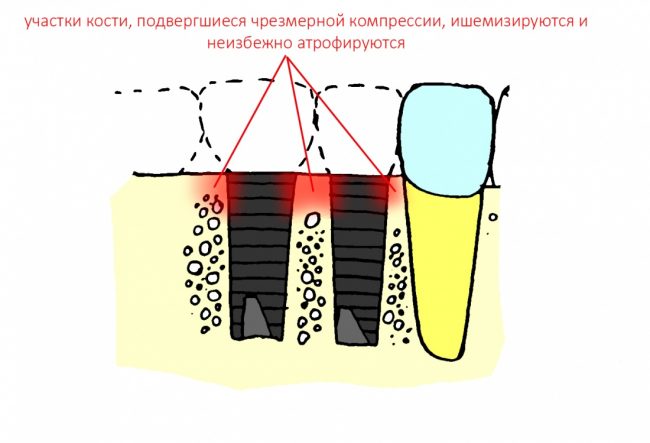

Однако, есть один нюанс, к которому любят апеллировать, если речь идет о позиционировании. Это расстояние между имплантатами, либо имплантами и естественными зубами.

Существует мнение, что между имплантатами, или имплантами и зубами должно быть выдержано определенное расстояние, по данным ряда авторов, от 1,5 до 3 мм, и это, как считается, необходимо для сохранения костной ткани. Типа, если между имплантатами останется совсем небольшой слой кости, то он потеряет питание, атрофируется — и превед, периимплантит. Этим мнимым правилом любят прикрываться, если речь идёт о неправильном позиционировании или неправильном подборе имплантов — дескать, «я выдерживал расстояние!». Или, что еще хуже, предлагают пациенту удалить, к примеру, нижние резцы по бокам от дефекта зубного ряда — типа, иначе не будет держаться…

Вместе с тем, существует масса примеров, когда костная ткань уходила, даже если имплантаты стояли на расстоянии 5 мм друг от друга:

Для начала, обратимся к расстоянию между естественными зубами и измерим межальвеолярные перегородки. Их ширина может быть значительно меньше миллиметра, но при этом они не атрофируются и не теряют высоту. Мы знаем, что сквозь корни зубов сосуды не растут — а это значит, что они как-то кровоснабжаются и при такой толщине верно? Следовательно, история о том, что «для кровоснабжения кости нужна какая-то определенная толщина» — не более, чем заблуждение:

Заменим зуб на имплантат. Что принципиально изменилось?

С точки зрения геометрии — ничего, как была перегородка, так она и осталась. Так почему же в некоторых случаях мы наблюдаем атрофию и потерю кости между имплантатами?

Не поверите, но проблема не столько в расстоянии, сколько в том, как мы готовим лунки под имплантат. В прорезывании зубов и «прорезывании» имплантатов есть принципиальное отличие — если первые не прорезываются мгновенно, и у костной ткани межкорневой перегородки есть время на построение и формирование микроциркуляторного русла, то при установке вторых мы мало того, что травмируем — мы зажимаем костную ткань между двумя несжимаемыми имплантатами, ишемизируя и без того плохо кровоснабжающийся участок:

и получаем закономерный результат — всё, что остаётся без питания, обижается и ,рано или поздно, уходит.